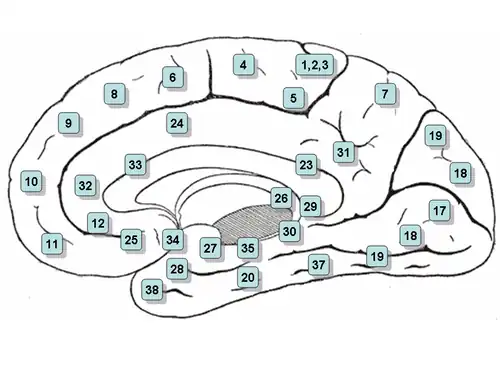

Medial surface of left cerebral hemisphere, with anterior cingulate highlighted | |

Medial surface of right hemisphere, with Brodmann's areas numbered | |

In human brains, the anterior cingulate cortex (ACC) is the frontal part of the cingulate cortex that resembles a "collar" surrounding the frontal part of the corpus callosum. It consists of Brodmann areas 24, 32, and 33.